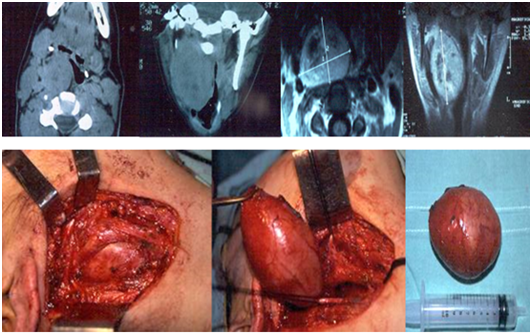

Two patients had neurilemomas located at the nasal cavity. One of them, consulted for left nasal obstruction and another for epistaxis and bilateral disturbance of visual acuity.

They were evaluated by tomography and MRI. A neoplasm was located at the anterior area of the left nostril, and another had an endocranial origin, and had extension to the nasal cavity, eroding the lamina cribosa. In both cases, a biopsy was performed, and the diagnosis was schwannoma. The nerve of origin in both cases was the trigeminal. A neoplasm was completely resected by a sublabial approach, and in the other case, through a craneonasal approach. When performing the anterior craniotomy, it was found that the tumor was englobing the optical chiasm and the proximal area of both optic nerves, so a partial and conservative resection was performed. The patient with the nasal cavity neurilemoma had no neurological deficit.

The post operatory controls did not detect a recurrence during a 5-year follow-up in the case of the nasal tumor, and the patient with the intracranial neurilemoma with nasal extension had a better quality of life and improvement in visual acuity during the 2-year follow-up with residual tumor (Figure 8).

Figure 8 Neurilemoma originated at the trigeminal nerve.